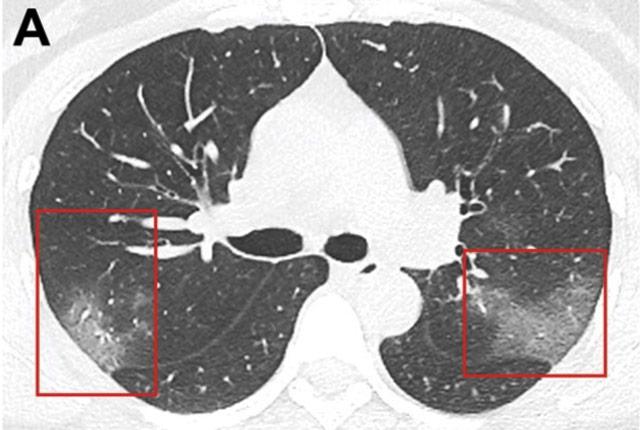

Aiming to improve the precision of COVID-19 diagnostics, U.S. radiologists, medical physicists, and computer scientists have created a massive virtual library. Its collection of x-rays and CT scans are intended to mobilize artificial intelligence against the novel coronavirus.

Medical imaging helps radiologists detect and monitor disease. Computer engineers are actively developing algorithms, based on x-rays and CT scans, to generate a probability that someone has COVID-19. These algorithms have been created based on a small number of images, but “our best estimates suggest we should be testing these algorithms on something like 10,000 images,” Kinahan said. “We want to avoid time spent developing algorithms whose logic is based on too few patient samples, because ultimately, the algorithm’s projections will fail to hold up.”

To test, train, and validate machine-learning algorithms, hundreds of thousands of scans must first be collected, de-identified, and curated so they are free of artifacts – visual “noise” created by the scanning technology – and then uploaded to the database.